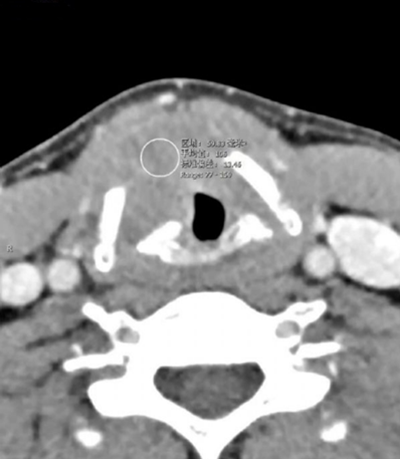

声门层面右侧声带增厚,呈结节状软组织密度影,边界尚可见,前联合及左侧声带前1/2受累,声门左偏,周围脂肪间隙小时,右侧甲状软骨骨质破坏。增强扫描呈轻度延迟强化。